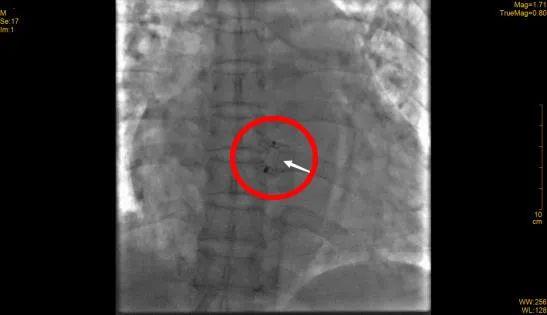

徐先增团队顺利为患者放入封堵器

完善相关检查后,徐先增团队为农先生实施了介入封堵术。仅40分钟,他们便顺利将封堵器放入异常通道并将其固定。经查,农先生的右主动脉、右心室已恢复“泾渭分明”的状态。